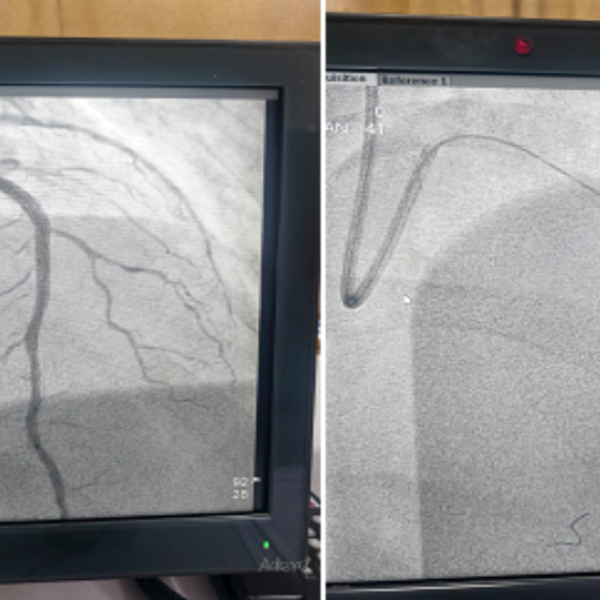

- Catheter Insertion: They guide a thin, flexible tube (catheter) to the heart using X-ray imaging and echocardiography.

- Device Placement: Doctors deliver the closure device, typically a self-expanding mesh or umbrella-like structure, to the defect site through the catheter.

- Sealing the Defect: The device expands and seals the hole, allowing the heart to function normally.

- Verification: Doctors confirm proper device placement using imaging before removing the catheter.